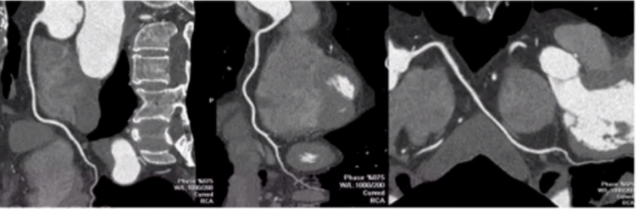

2、曲面重建

看血管狭窄与肌桥。曲面重建是将弯曲走形的冠状动脉通过后处理软件在同一个二维平面上显示同一根血管,一般显示2-3个图像(像做冠脉造影一样,对于同一根血管会做多个体位评估血管情况)。

图14